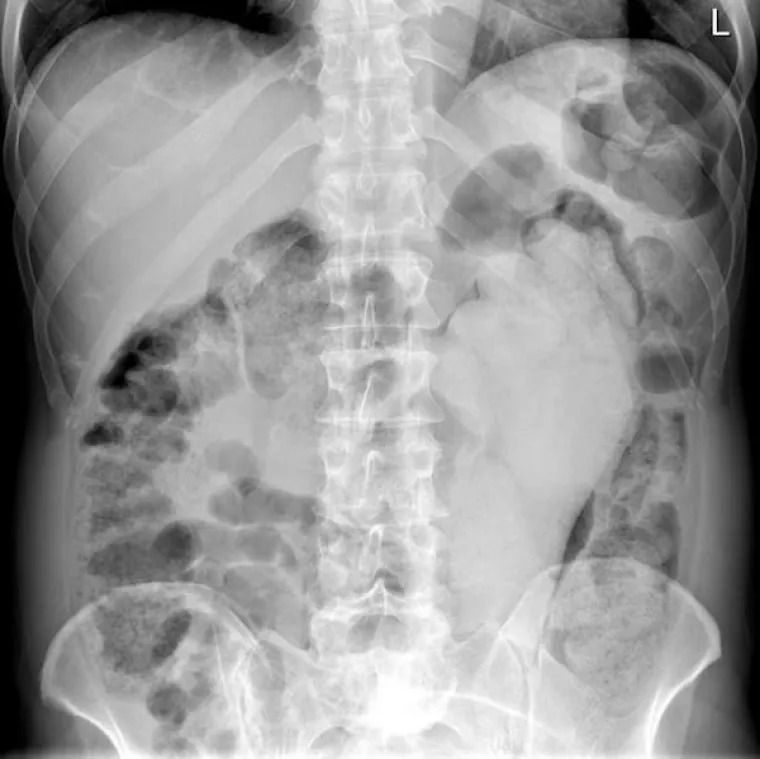

LJUDI SU ČAROBNO SPREMIŠTE, U NJIH STANE BAŠ SVE: Nevjerojatne snimke pokazuju što su sve uspjeli ugurati u sebe